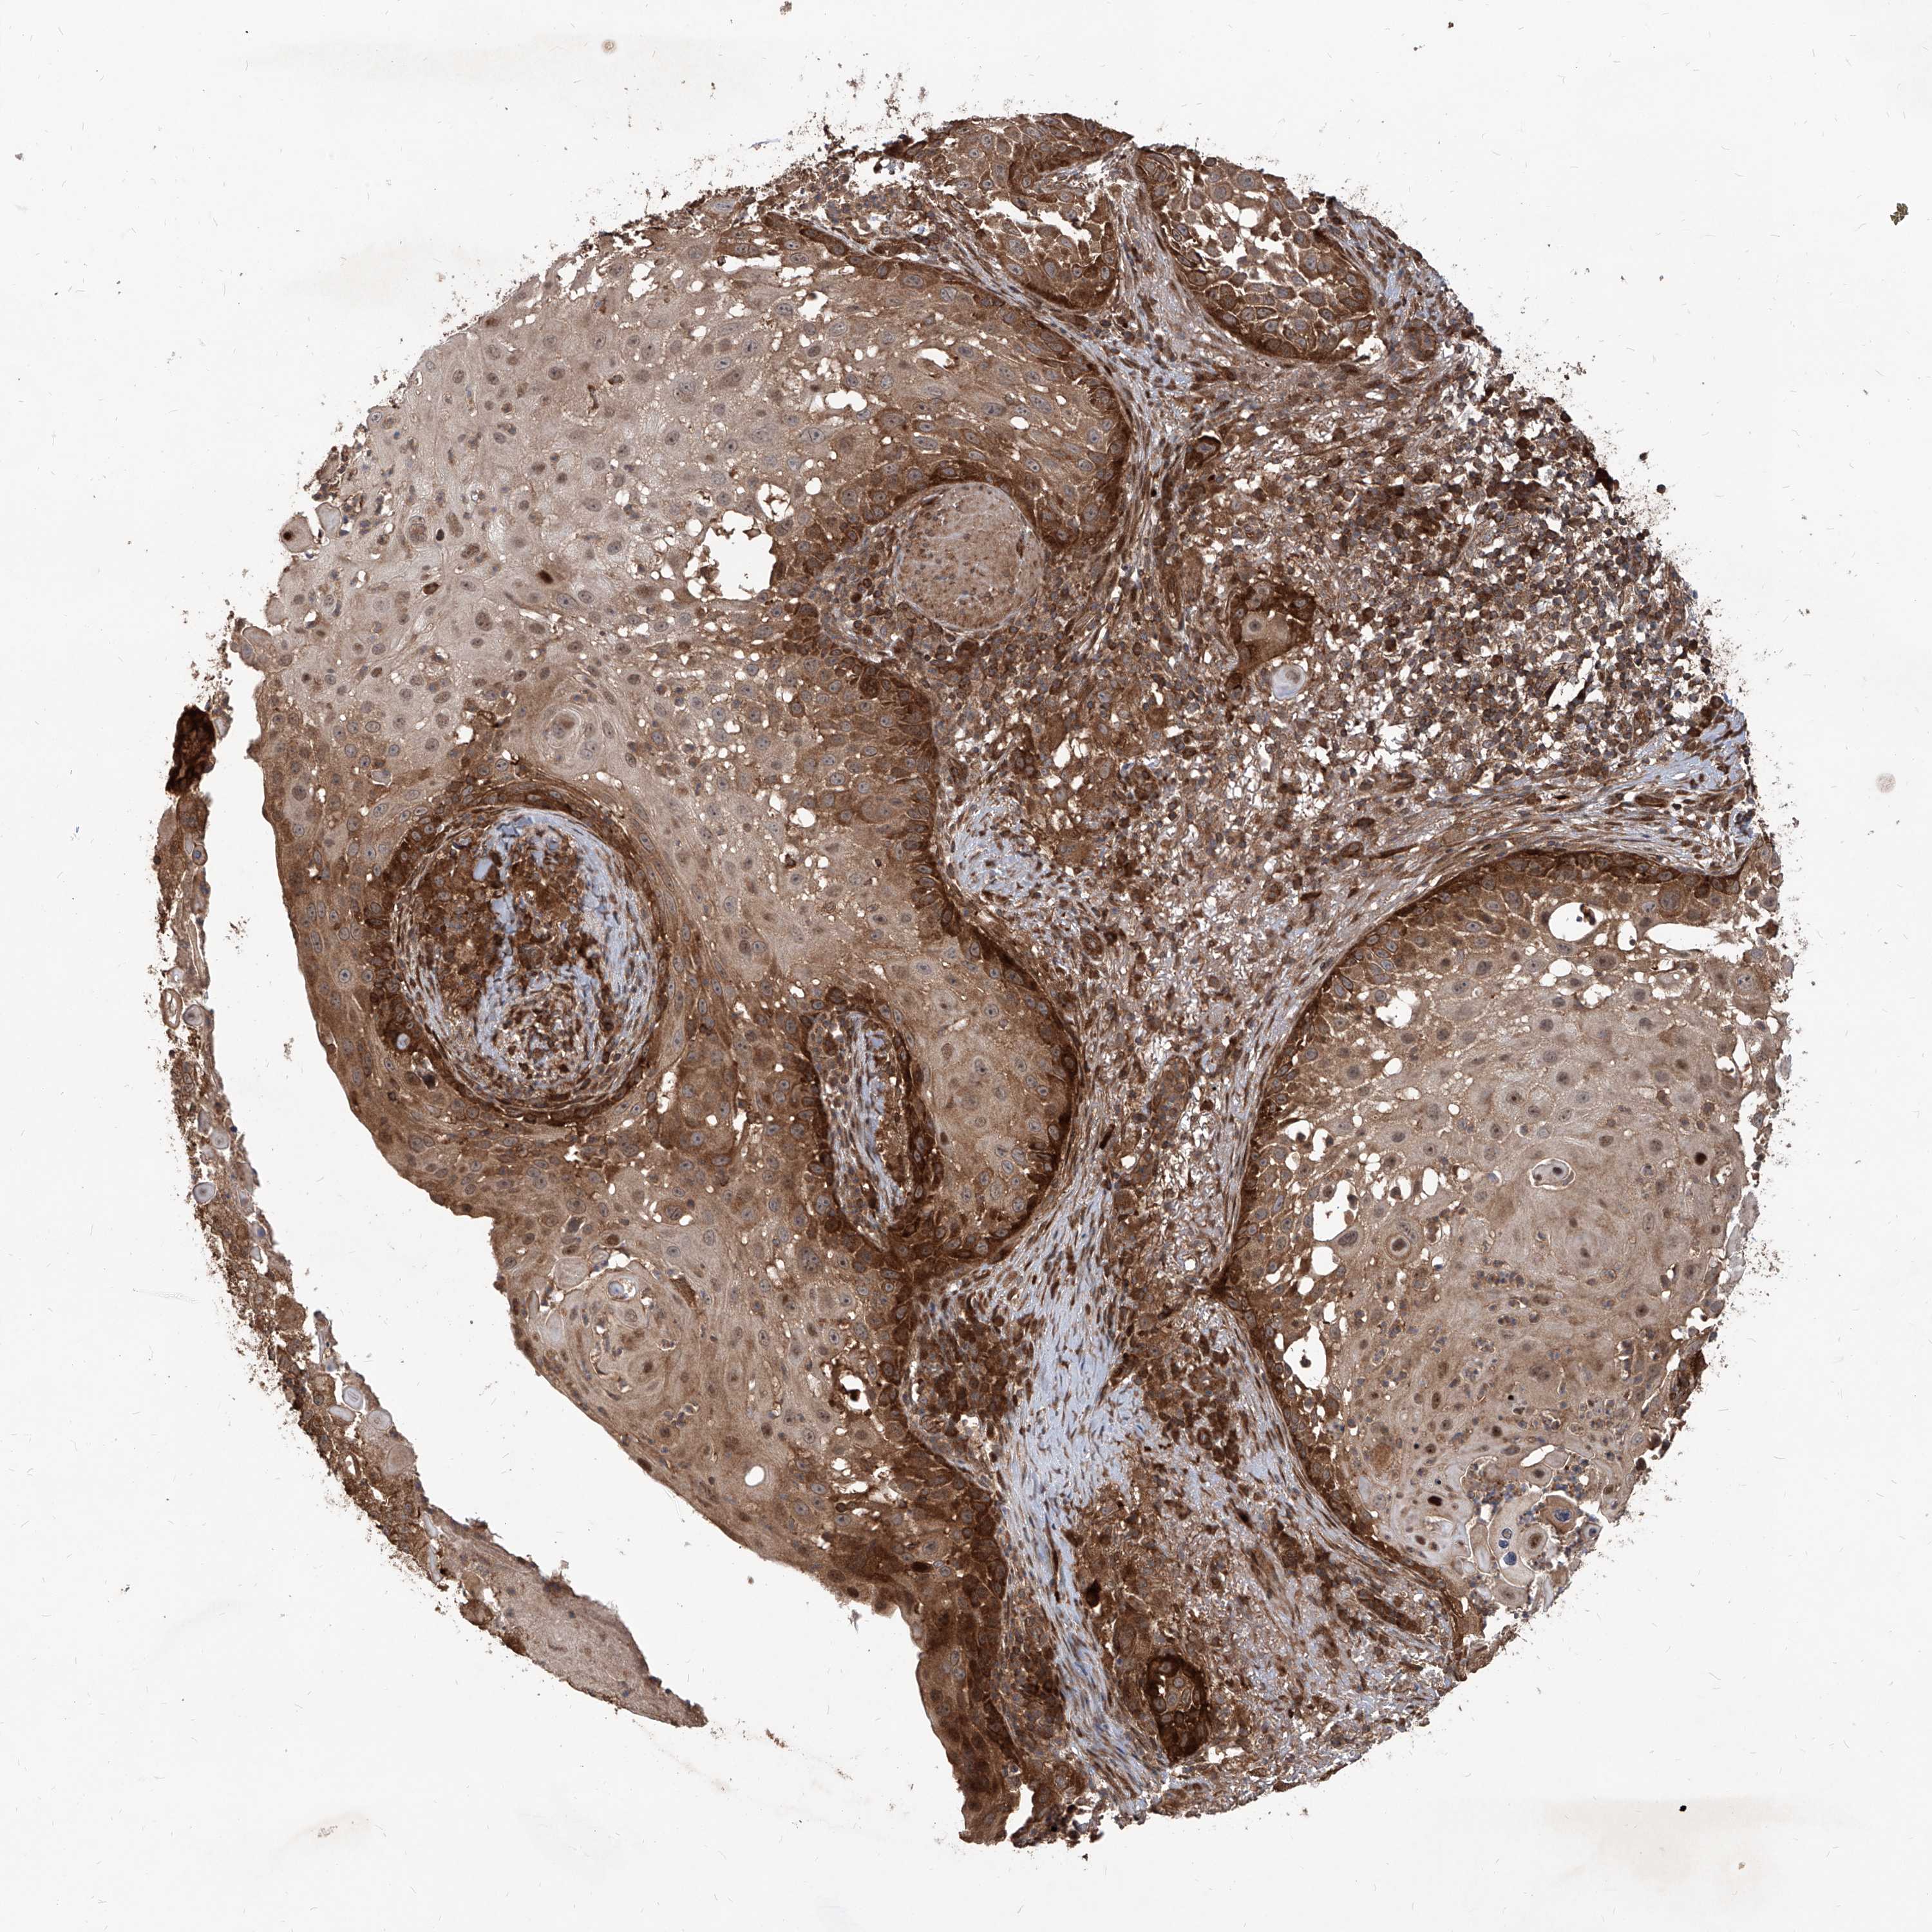

Basal cell and squamous cell cancer

SKIN CANCER - Protein expressioni

A mouse-over function shows sample information and annotation data. Click on an image to view it in a full screen mode. Samples can be filtered based on level of antibody staining by selecting one or several of the following categories: high, medium, low and not detected. The assay and annotation is described here.

Antibody stainingi

Antibody staining in the annotated cell types in the current human tissue is reported as not detected, low, medium, or high, based on conventional immunohistochemistry profiling in selected tissues. This score is based on the combination of the staining intensity and fraction of stained cells.

Each image is clickable and will lead to virtual microscopy that enables deeper exploration of all samples and also displays staining intensity scores, fraction scores and subcellular localization as well as patient and tissue information for each sample.

Antibody HPA031572

Staining

High

Medium

Low

Not detected

Intensity

Strong

Moderate

Weak

Negative

Quantity

>75%

75%-25%

<25%

None

Location

Nuclear

Cytoplasmic/membranous

Cytoplasmic/membranous,nuclear

Basal cell carcinoma